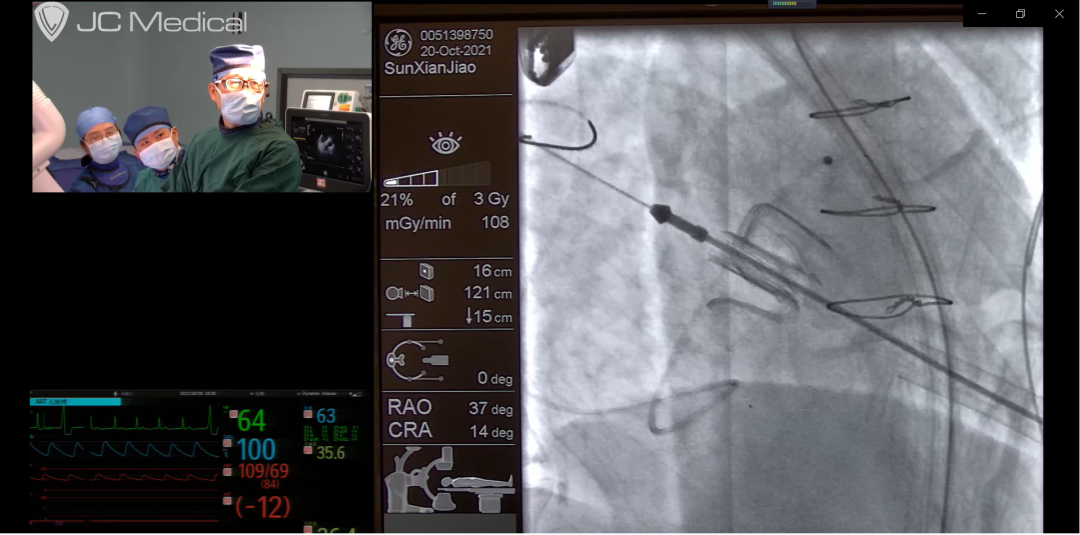

中国微创心外科大会直播生物瓣毁损的微创介入瓣中瓣手术

日前2021年中国微创心外科大会邀请张海波教授团队转播2台二尖瓣毁损的瓣中瓣手术。两例患者均为高龄,二尖瓣生物瓣置换术后十余年,瓣膜毁损后出现心衰、浮肿、胸腔积液等临床症状,反复救治多家医院因为年龄较大多脏器功能不全而认为再次开胸体外循环换瓣手术风险大,此次均为慕名前来安贞医院心外科瓣膜中心救治。2台手术分别采用国产J Valve瓣膜和国产百仁瓣膜,手术均获得顺利成功,国内有能力同时完成不同介入瓣膜的瓣中瓣技术仅有两三家大型中心。核心操作时间仅仅几分钟的时间,整个流程行云流水,术后造影和三维超声显示介入瓣膜功能良好,术前的瓣膜毁损的大量反流和重度狭窄消失,左房压力和肺动脉压即刻明显下降,手术效果立竿见影非常成功,获得了与会网络嘉宾专家的称赞。